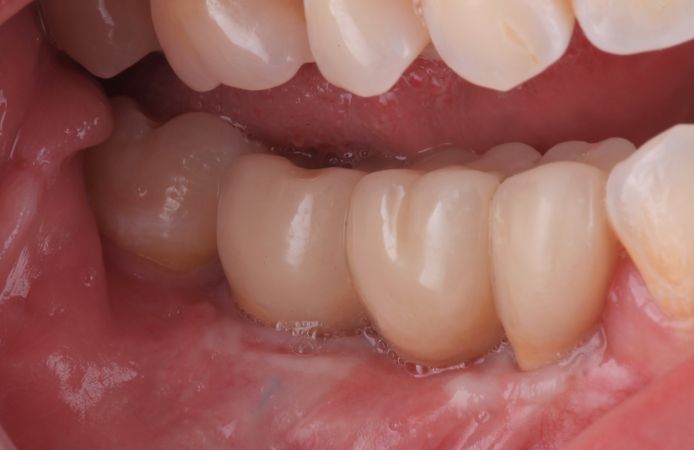

Figure 12.

Final restoration delivered six months after implant placement. The tissue levels are stable around the restoration with a satisfactory esthetic result.